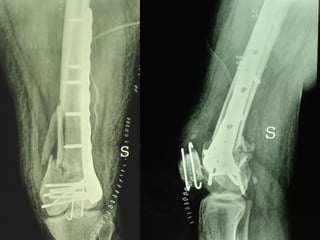

Dal Gennaio 2000 al Febbraio 2006 abbiamo trattato 167 fratture chiuse  con placca percutanea  in 164 pazienti :  27 lesioni diafisarie di gamba, 12 piloni tibiali ,  11 fratture prossimali di tibia, 36 fratture sovracondiloidee di femore, 17 fratture diafisarie di femore, 43 fratture metaepifisarie prossimali di omero, 21 diafisarie d’omero.  156 guarigioni 8 fallimenti

INDICAZIONI COMUNI Fratture sovracondiloidee Fratture intercondiliodee Fratture diafisarie distali PARTICOLARI Fratture con grave osteoporosi Fratture periprotesiche

VANTAGGI CHIRURGIA MININVASIVA Mini Open Inserimento della placca sottocutaneo per scivolamento Viti percutanee Preservazione dei tessuti molli Ridotto danno vascolare Rapida ripresa funzionale

Conclusioni Riduzione  anatomica Minimo trauma chirurgico Corretto equilibrio fra elasticità e stabilità Precoce mobilizzazione